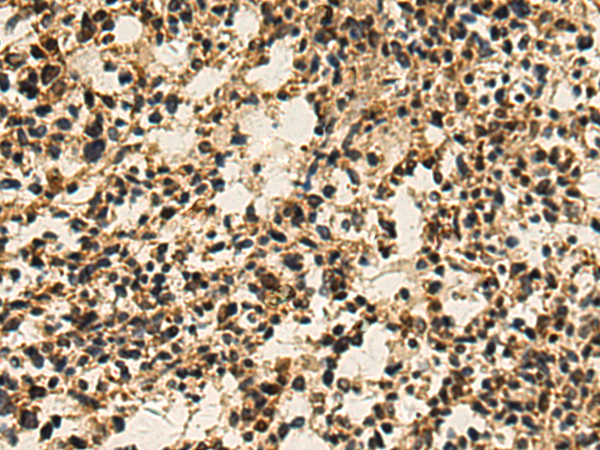

The image is immunohistochemistry of paraffin-embedded Human ovarian cancer tissue using (PRELP Antibody) at dilution 1/120.